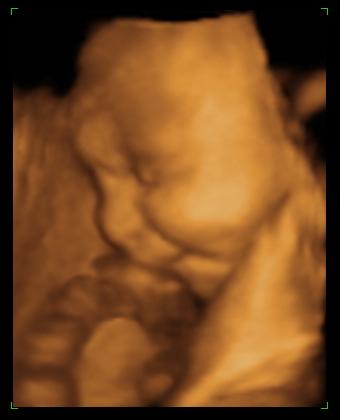

egy bukfenc